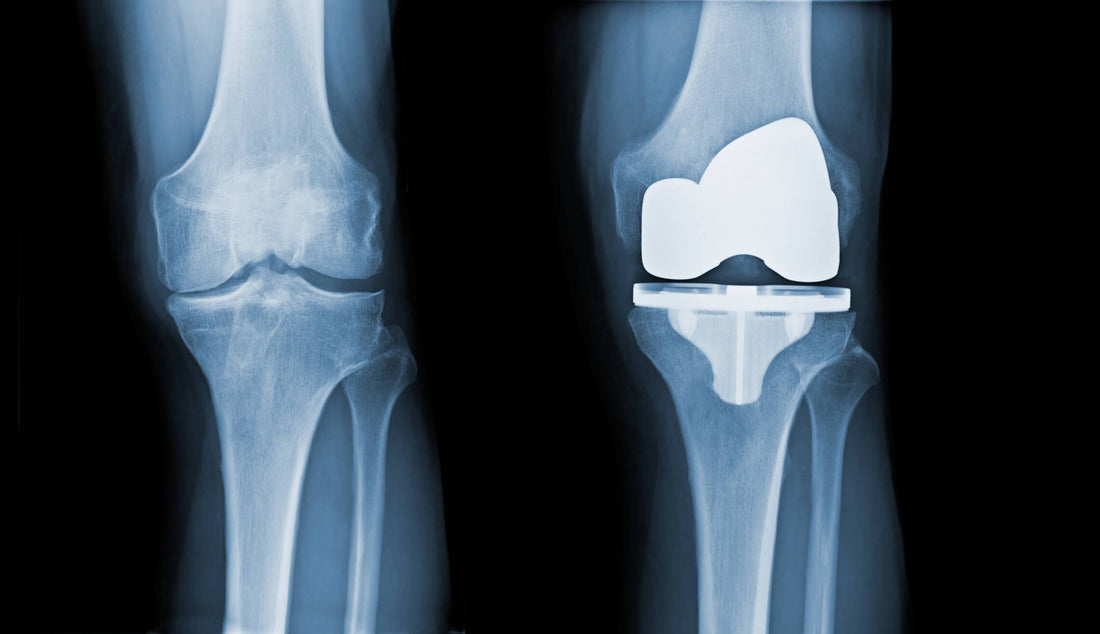

"How long will my new knee last?" It's one of the most common and important questions we hear in Physiotherapy clinics. Until recently, the answer was based on limited data. Now, a landmark systematic review and meta-analysis published in The Lancet provides one of the most comprehensive answers to date, analysing data from over 300,000 knee replacements.

The Bottom Line: The research found that 82% of total knee replacements (TKRs) and 70% of partial knee replacements (UKRs) last for 25 years. However, the longevity of the implant itself may only be part of the story for long-term success.

The study, led by Evans et al., synthesised data from two primary sources: published case series and national joint replacement registries. By pooling results from sources like the Australian and Finnish registries, they achieved a much larger and more reliable sample size than any single study could provide. (1)

The primary outcome was "all-cause revision" – meaning any surgery to remove or replace part of the knee implant for any reason, including infection, loosening, instability, or persistent pain.